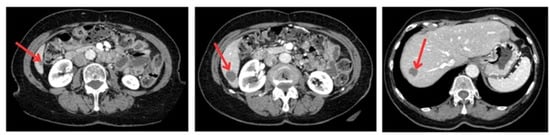

To generate a 3D liver phantom with three metastases, high-resolution CT images (512 × 512 pixels, slice thickness and interslice spacing of 1.25 mm) were acquired in both portal and arterial phases using a GE Healthcare Bright Speed Elite scanner. The acquisition period was 3 min and 45 s, with a tube voltage of 120 kVp and a current of 35 mA. These phases are essential for accurately characterizing liver tumors and visualizing the vascular architecture. The images were recorded in DICOM format to preserve essential acquisition metadata and ensure compatibility with medical imaging software. The anonymized images, providing optimal spatial resolution, were sourced from the Medical Segmentation Decathlon open-access dataset, ensuring data quality and reproducibility for segmentation and 3D modeling (Figure 2).

Figure 2. CT images of a patient with liver metastases. The red arrows indicate the location of metastatic lesions in the liver and surrounding anatomical regions visible in the axial CT slices.